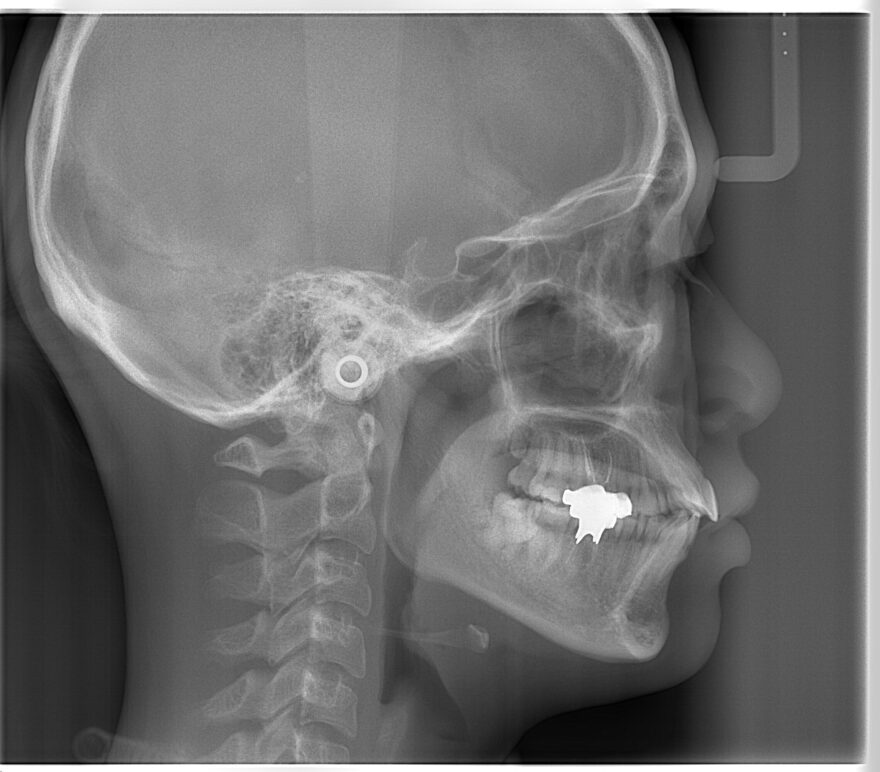

- 矯正資料どり(写真・レントゲン撮影や口腔内の型どり等)

- 矯正診断(芝田Dr.との相談)

私の場合は、矯正前に治さないといけない箇所が多く、また親知らずも全て抜歯する必要があったので、スタートまでに数カ月かかってしまいました!!